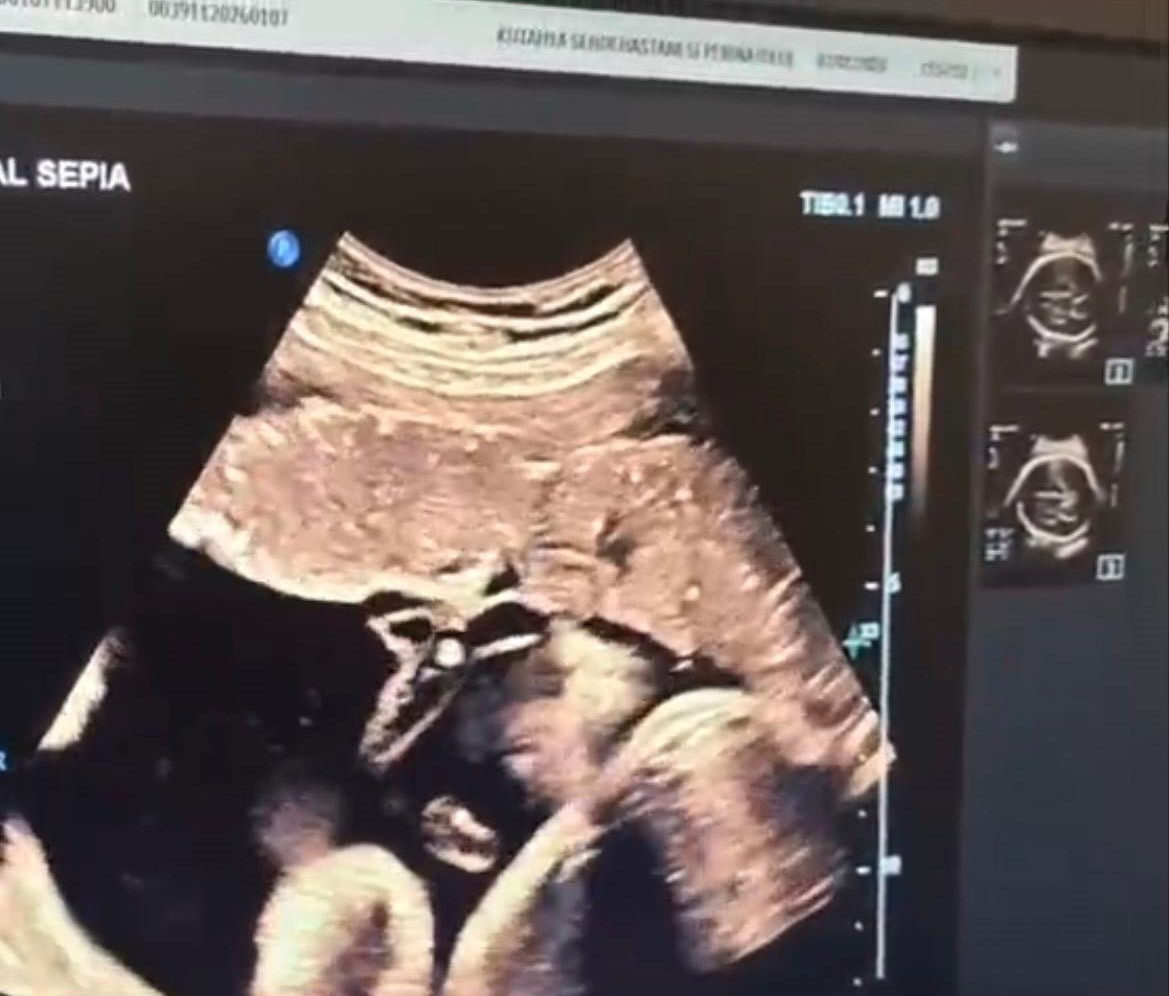

Halk arasında “anne karnında kan nakli” olarak bilinen intrauterin fetal kan transfüzyonu, bebekte ciddi kansızlık (anemi) tespit edilmesi halinde uygulanan hayati bir tedavi yöntemi olarak biliniyor. İşlem, ultrason eşliğinde anne karnından ince bir iğne yardımıyla bebeğin göbek kordonuna girilerek gerçekleştiriliyor. Önce bebeğin kan değerleri ölçülüyor, ardından eksik olan miktar kontrollü şekilde naklediliyor. Lokal anestezi altında ve steril şartlarda yapılan müdahale yaklaşık 30-45 dakika sürüyor.